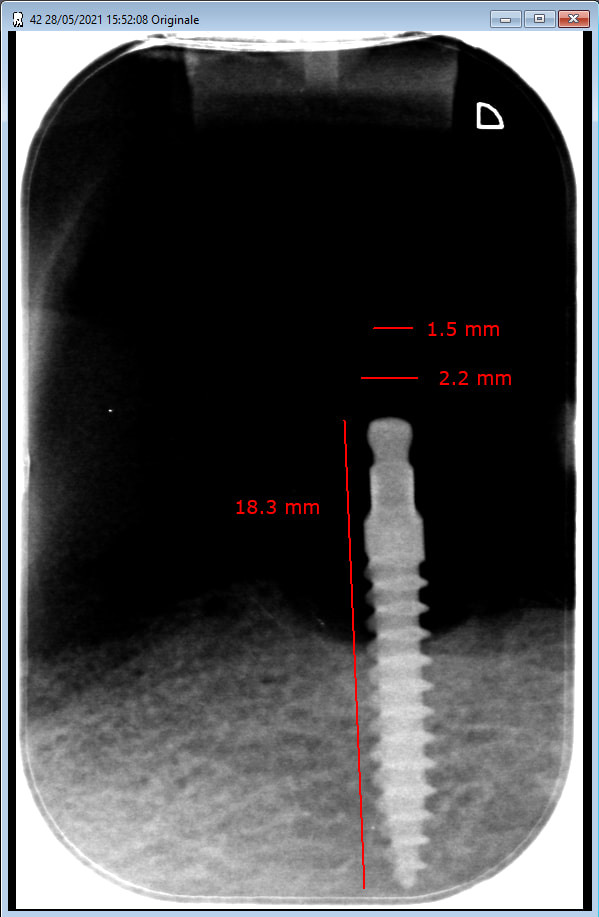

Implants posés en 2005, je suis a la recherche d'attachements femelles compatibles pour refection d'un complet bas...

Ca ressemble à ça non ?

https://www.c-tech-implant.com/en/implants/mini-dental-implants

pas d'accord pour la ressemblance de la géometrie partie attachement et par là une compatibilité des pièces prothetiques , compléments demandés à Hokusai en MP.